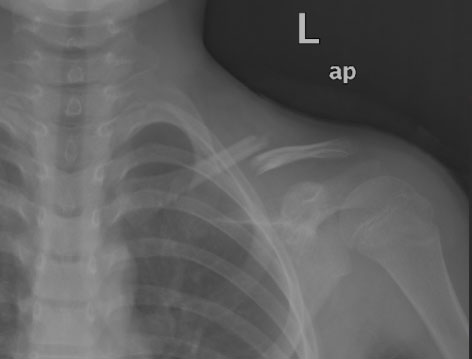

兒童鎖骨骨折怎么辦?

鎖骨為一長管狀骨,橋架于肩胛骨與軀干之間鎖骨位于胸廓的頂部前方,全長位于皮下,為上肢帶與軀干連接的惟一骨性結(jié)構(gòu),易遭受外力發(fā)生骨折,在兒童時期尤為多見。

輕微的跌傷即可出現(xiàn)兒童鎖骨骨折,但因兒童不能準(zhǔn)確表述而容易被漏診。當(dāng)?shù)鴤鹿钦酆髢和R蚣绮刻弁磳⒒紓?cè)上臂靠在胸壁上,或以健手托住患側(cè)肘部?;純侯^常傾斜向患側(cè),以緩解因胸鎖乳突肌牽拉引起的疼痛。對于部分幼兒及新生兒鎖骨骨折,可表現(xiàn)為肢體不愿活動及局部拒絕觸碰、哭鬧等,需要細致檢查才能避免漏診。

對無移位的鎖骨以 “8”字繃帶固定即可,對有成角畸形者,復(fù)位后仍以 “8”字繃帶維持對位。鎖骨骨折并不要求完全達到解剖對位,只要不是非常嚴(yán)重的移位,骨折愈合后均可獲得良好的功能。

骨折移位明顯經(jīng)手法復(fù)位仍嚴(yán)重畸形的患者可行手術(shù)治療。對于部分大齡兒童,由于對復(fù)位要求高或患者要求盡早返校學(xué)習(xí),可以考慮手術(shù)治療。我院小

兒骨科采用國內(nèi)外最先進的彈性髓內(nèi)釘固定手術(shù)治療,在微創(chuàng)的基礎(chǔ)上可以盡量解剖復(fù)位骨折,牢固固定,早期功能鍛煉,治療效果確切。

當(dāng)然發(fā)現(xiàn)鎖骨骨折的同時,應(yīng)警惕其他的合并損傷,如氣胸,胸部、肩部的骨折以及神經(jīng)、血管損傷等。